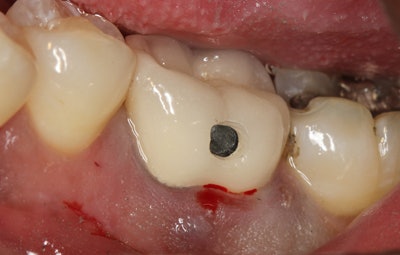

A product I recently evaluated, the WAMkey (Golden Dental Solutions), has changed how I approach the removal of crowns and bridges (figure 4). The Wamkey Intro Kit contains three keys in oval-shaped heads: sizes small, medium, and large.

- Create a small window in the crown that is approximately 1 mm to 2 mm in diameter where the preparation/crown occlusal interface is assumed to be located (figure 5). The opening should be made closer to the occlusal surface for metal crowns and generally about halfway between the occlusal surface and the margin for porcelain or PFM crowns.